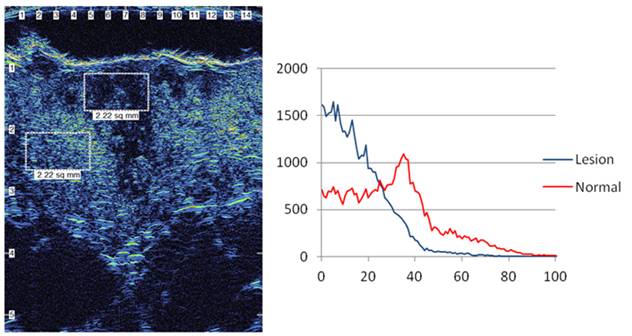

Trả lời: Trước hết chúng tôi rất cảm ơn câu hỏi của bạn, liên quan đến vấn đề siêu âm da để đánh giá gián tiếp hình ảnh và loại thương tổn da và các cơ quan liên quan trong các bệnh lý da hiện nay. Trên thực tế có thể sử dụng nhiều cách siêu âm da, nhân đây chúng tôi xin giới thiệu với bạn về siêu âm da bằng máy UV Scanner. Trên thực tế, rất ít người hiểu chính xác về tình trạng làn da của mình, da không chỉ bảo vệ cơ thể mà còn là tiếng nói cho sức khỏe và là yếu tố tiên quyết tạo nên vẻ đẹp thẩm mỹ. Chúng ta luôn âu lo khi thấy da xuất hiện những dấu hiệu xấu nhưng lại không biết nguyên nhân xuất phát từ đâu. Siêu âm da là cách để bạn giải tỏa những băn khoăn này và xác định được phương pháp chăm sóc điều trị da thích hợp, tiết kiệm thời gian, chi phí, đem lại hiệu quả cao.

Công nghệ siêu âm UV Scaner sử dụng thiết bị đa cảm biến, cùng lúc chẩn đoán về độ ẩm, độ đàn hồi, độ sáng, nhiệt độ của da, kích cỡ lỗ chân lông. Với hiệu ứng 3D, hiển thị hiệu ứng tần số về tình trạng da, cùng chức năng tia tử ngoại giúp đo từng nanomet của lỗ chân lông, nếp nhăn và sự biến đổi sắc tố. Đặc biệt, máy có thể chẩn đoán chính xác da ngay cả khi bạn đã trang điểm. Trong khi các máy thông thường chỉ có thể đo lường trên bề mặt như kiểm soát mụn, vết thâm và khó dự đoán được mức biến đổi da của bạn trong tương lai thì chiếc máy này không chỉ dự đoán được mức lão hóa của da bạn mà còn kiểm soát sâu, toàn bộ tình hình và các bệnh lý về da, từ đó các bác sĩ sẽ cho bạn lời khuyên về chế độ chăm sóc kịp thời và hợp lý nhất.

H2

Trên đây là một ví dụ cho thấy siêu âm có thể đơn thuần hoặc phối hợp trong chẩn đoán và điều trị một số bệnh ngoài da có giá trị. Bạn có thể tìm đọc thêm trên các trang mạng với từ khóa google.com/ skin ultrasound